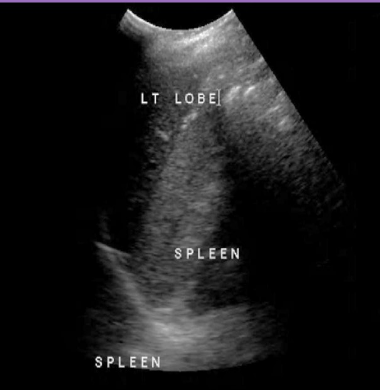

Identify this image.

Polycystic liver disease (PCLD)